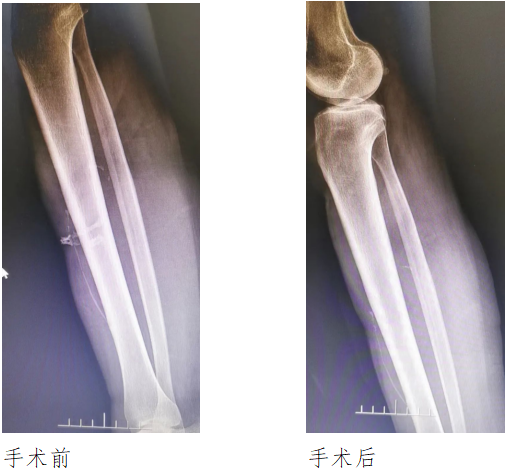

伤科医院手足科主任李康贵接待了黄女士,检查发现,在其右小腿中上段、右膝处有疤痕,右小腿前方正中的溃疡面积约2平方厘米,周围皮肤暗紫,有少许渗液,“溃疡面皮肤里有骨样物质外露,摸起来凸凹不平,周围还有2个小溃疡面。”

行手术治疗,“我们在术中将溃疡组织、钙化组织完全切除,辅以抗生素、换药及中医中药的辨证施治等,患者伤口愈合康复出院。”李康贵称。